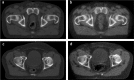

The recent advances in radiation delivery can improve tumour control probability (TCP) and reduce treatment-related toxicity. The use of intensity-modulated radiotherapy (IMRT) in particular can reduce normal tissue toxicity, an objective in its own right, and can allow safe dose escalation in selected cases. Ideally, IMRT should be combined with image guidance to verify the position of the target, since patients, target and organs at risk can move day to day. Daily image guidance scans can be used to identify the position of normal tissue structures and potentially to compute the daily delivered dose. Fundamentally, it is still the tolerance of the normal tissues that limits radiotherapy (RT) dose and therefore tumour control. However, the dose-response relationships for both tumour and normal tissues are relatively steep, meaning that small dose differences can translate into clinically relevant improvements. Differences exist between individuals in the severity of toxicity experienced for a given dose of RT. Some of this difference may be the result of differences between the planned dose and the accumulated dose (DA). However, some may be owing to intrinsic differences in radiosensitivity of the normal tissues between individuals. This field has been developing rapidly, with the demonstration of definite associations between genetic polymorphisms and variation in toxicity recently described. It might be possible to identify more resistant patients who would be suitable for dose escalation, as well as more sensitive patients for whom toxicity could be reduced or avoided. Daily differences in delivered dose have been investigated within the VoxTox research programme, using the rectum as an example organ at risk. In patients with prostate cancer receiving curative RT, considerable daily variation in rectal position and dose can be demonstrated, although the median position matches the planning scan well. Overall, in 10 patients, the mean difference between planned and accumulated rectal equivalent uniform doses was -2.7 Gy (5%), and a dose reduction was seen in 7 of the 10 cases. If dose escalation was performed to take rectal dose back to the planned level, this should increase the mean TCP (as biochemical progression-free survival) by 5%. Combining radiogenomics with individual estimates of DA might identify almost half of patients undergoing radical RT who might benefit from either dose escalation, suggesting improved tumour cure or reduced toxicity or both.